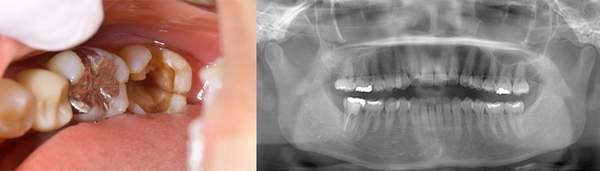

ブリッジが取れたということでご来院患者様でした。レントゲンを撮ると縦に割れていました。

歯を抜くと、やはり割れていました。

歯の破折で抜歯したものです。

断面をみてみえると黒くなっているのがわかります。これは全部細菌です。歯がわれてしまうと、隙間に細菌が住み付き、繁殖してしまいます。そのため、骨や歯茎の中で炎症を起こしてしまいます。破折に気づかず根の治療をしても効果が得られないのです。

こちらは、歯の根の治療を行い、根の先端までキレイにし、防腐剤をしっかり詰めなおしましたが、膿が溜まったまま治癒しませんでした。破折に気づけなかったのです。

破折に気づいてからは、抜歯を行い、インプラントを入れてまた噛める様にしていきました。レントゲンでも破折がわからない時があります。そんな時はCTやマイクロスコープを使うとわかることが多いのです。